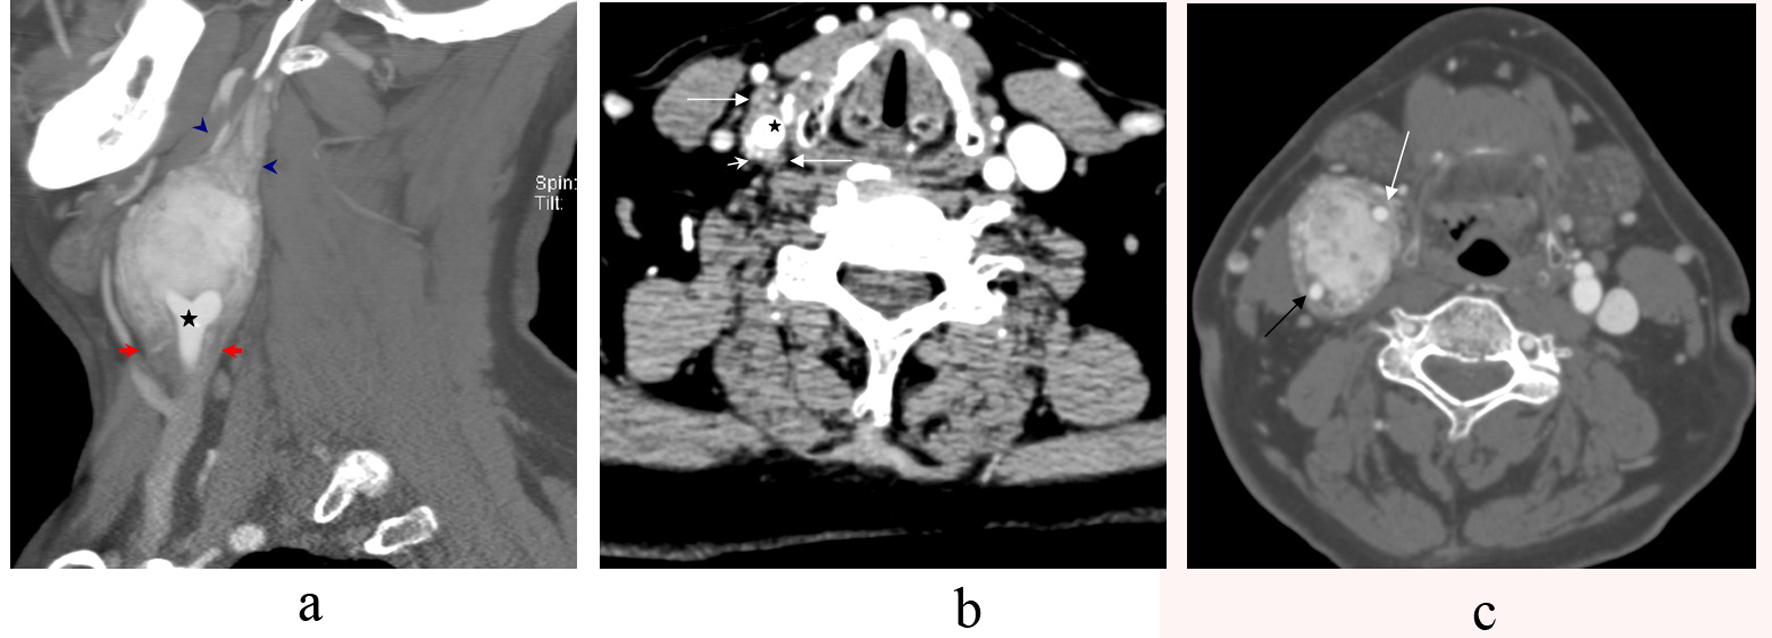

CT angiography of the neck demonstrated an avidly enhancing mass splaying the right external carotid artery (ECA) and the internal carotid artery (ICA). The mass begins 1.6 cm below the right CCA bifurcation with the bulk of the tumor measuring 4.3 x 3.4 x 5.8 cm. There was additional tumor projecting approximately 1.6 cm above the dominant mass. The right internal jugular vein is compressed (Fig. 1a-c).

![]() Click for large image | Figure 1. a-c. CT Angiography sagittal section showing a large carotid body tumor splaying the external carotid artery (ECA) and the internal carotid artery (ICA) at the level of th common carotid bifurcation (star). The tumor notably extends inferiorly 1.6 cm below the common carotid bifurcation (arrows). It also extends approximately 1.6 cm superiorly above the main bulk of the tumor (arrowhead) (a). Axial CT Angiography of the neck showing the tumor (long arrows) wrapping the common carotid artery (star) below the bifurcation with avid vascularity of the tumor (short arrows) (b). Axial CT Angiography section demonstrating an avidly enhancing mass splaying the internal carotid artery (black arrow) and the external carotid artery (white arrow) (c). |